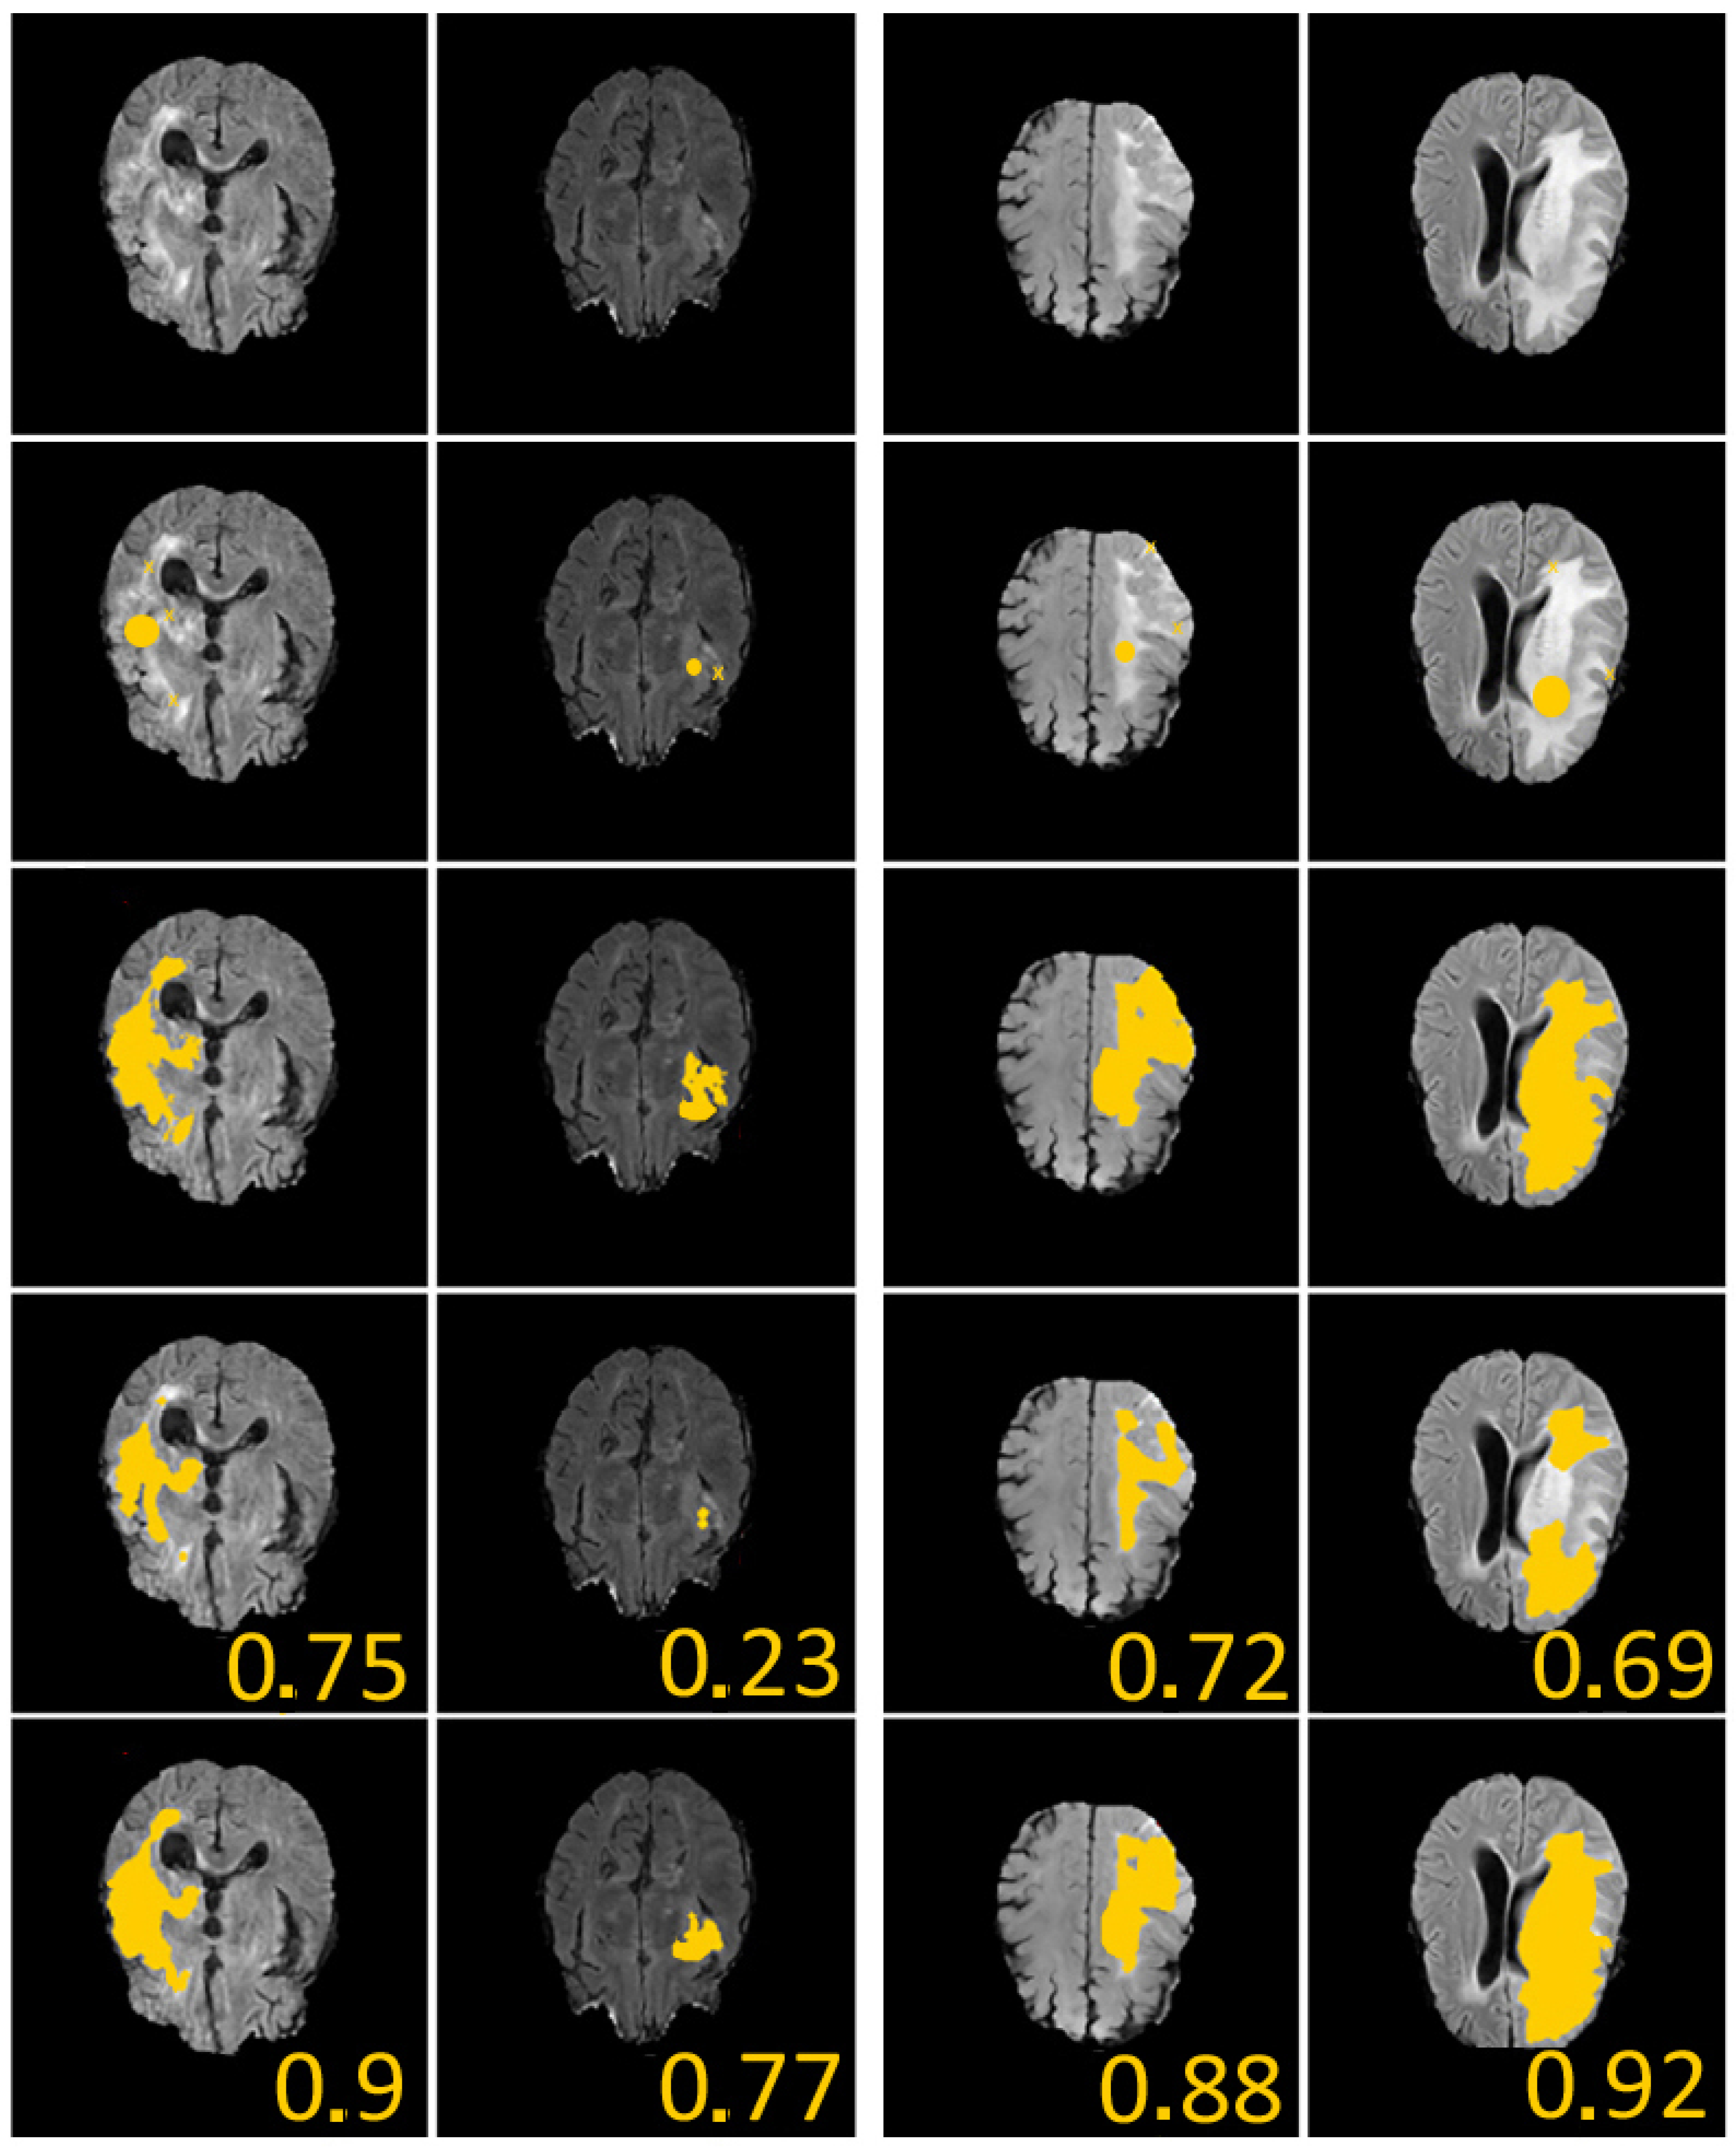

4.2. Image Segmentation

- and : it corresponds to our proposed segmentation model under geometric conditions.

- and : it corresponds to a basic segmentation model without geometric conditions.